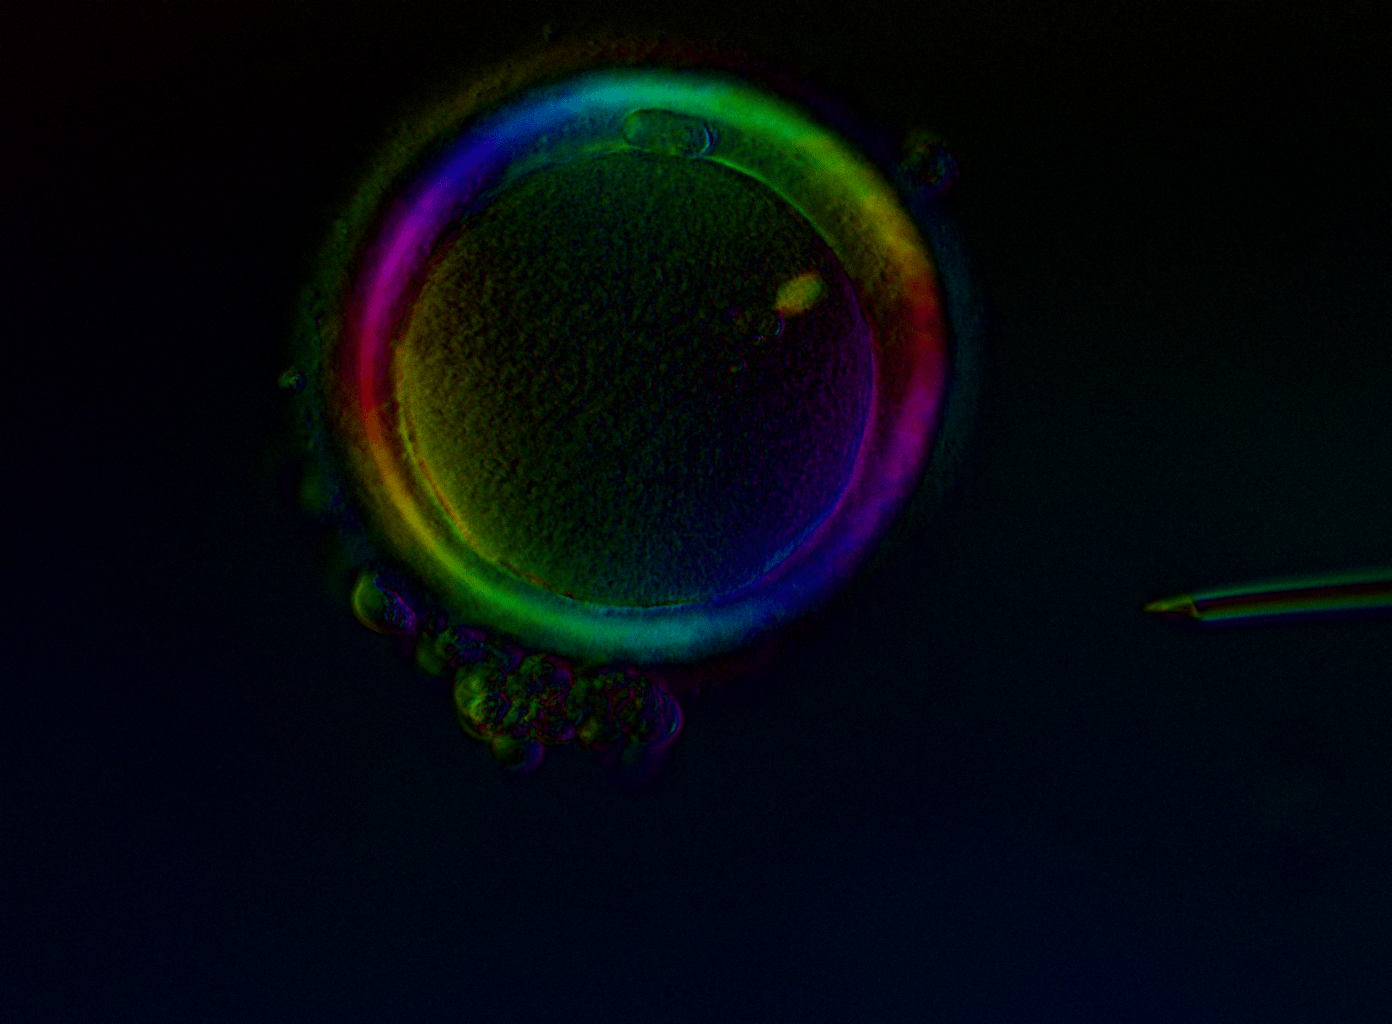

HOPE is the only laboratory that examines every single oocyte using polarised light microscopy before any clinical decision is made—whether for injection, freezing, or treatment planning. This is not an optional add-on; it is our standard of care for every patient.

Standard microscopy shows you what an egg looks like on the outside. Polarised light microscopy (Oosight™ Meta technology) reveals what is happening inside — specifically, the meiotic spindle, the structure where the egg's genetic material is organised.

This tells us whether an egg is truly mature at the genetic level, not just visually. It also allows us to assess the zona pellucida (the egg's protective shell) to evaluate the egg's developmental potential.